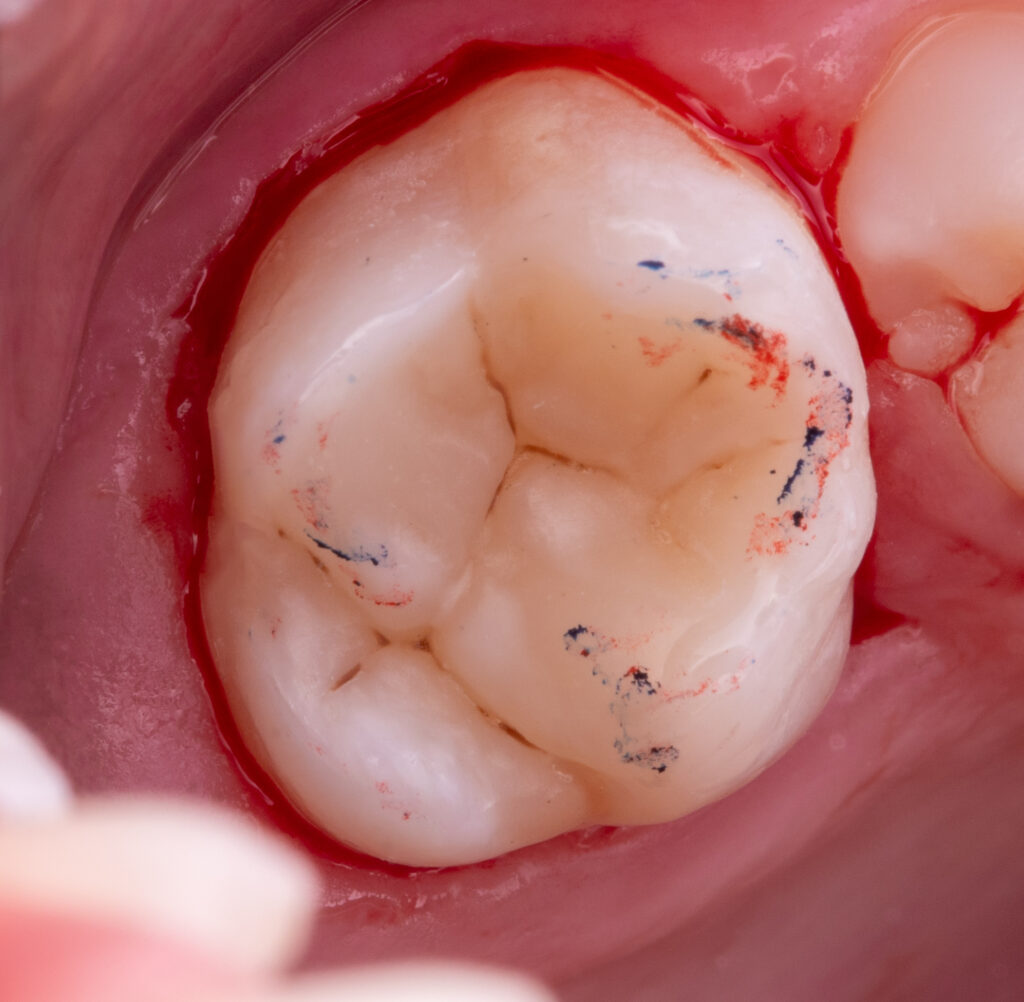

In a single visit, the old composite restoration was completely removed and replaced with a new composite (Asteria A2B / NeoSpectra A2).

EverX (flowable glass fiber composite) was used as a reinforcing layer to improve the strength and durability of the tooth.